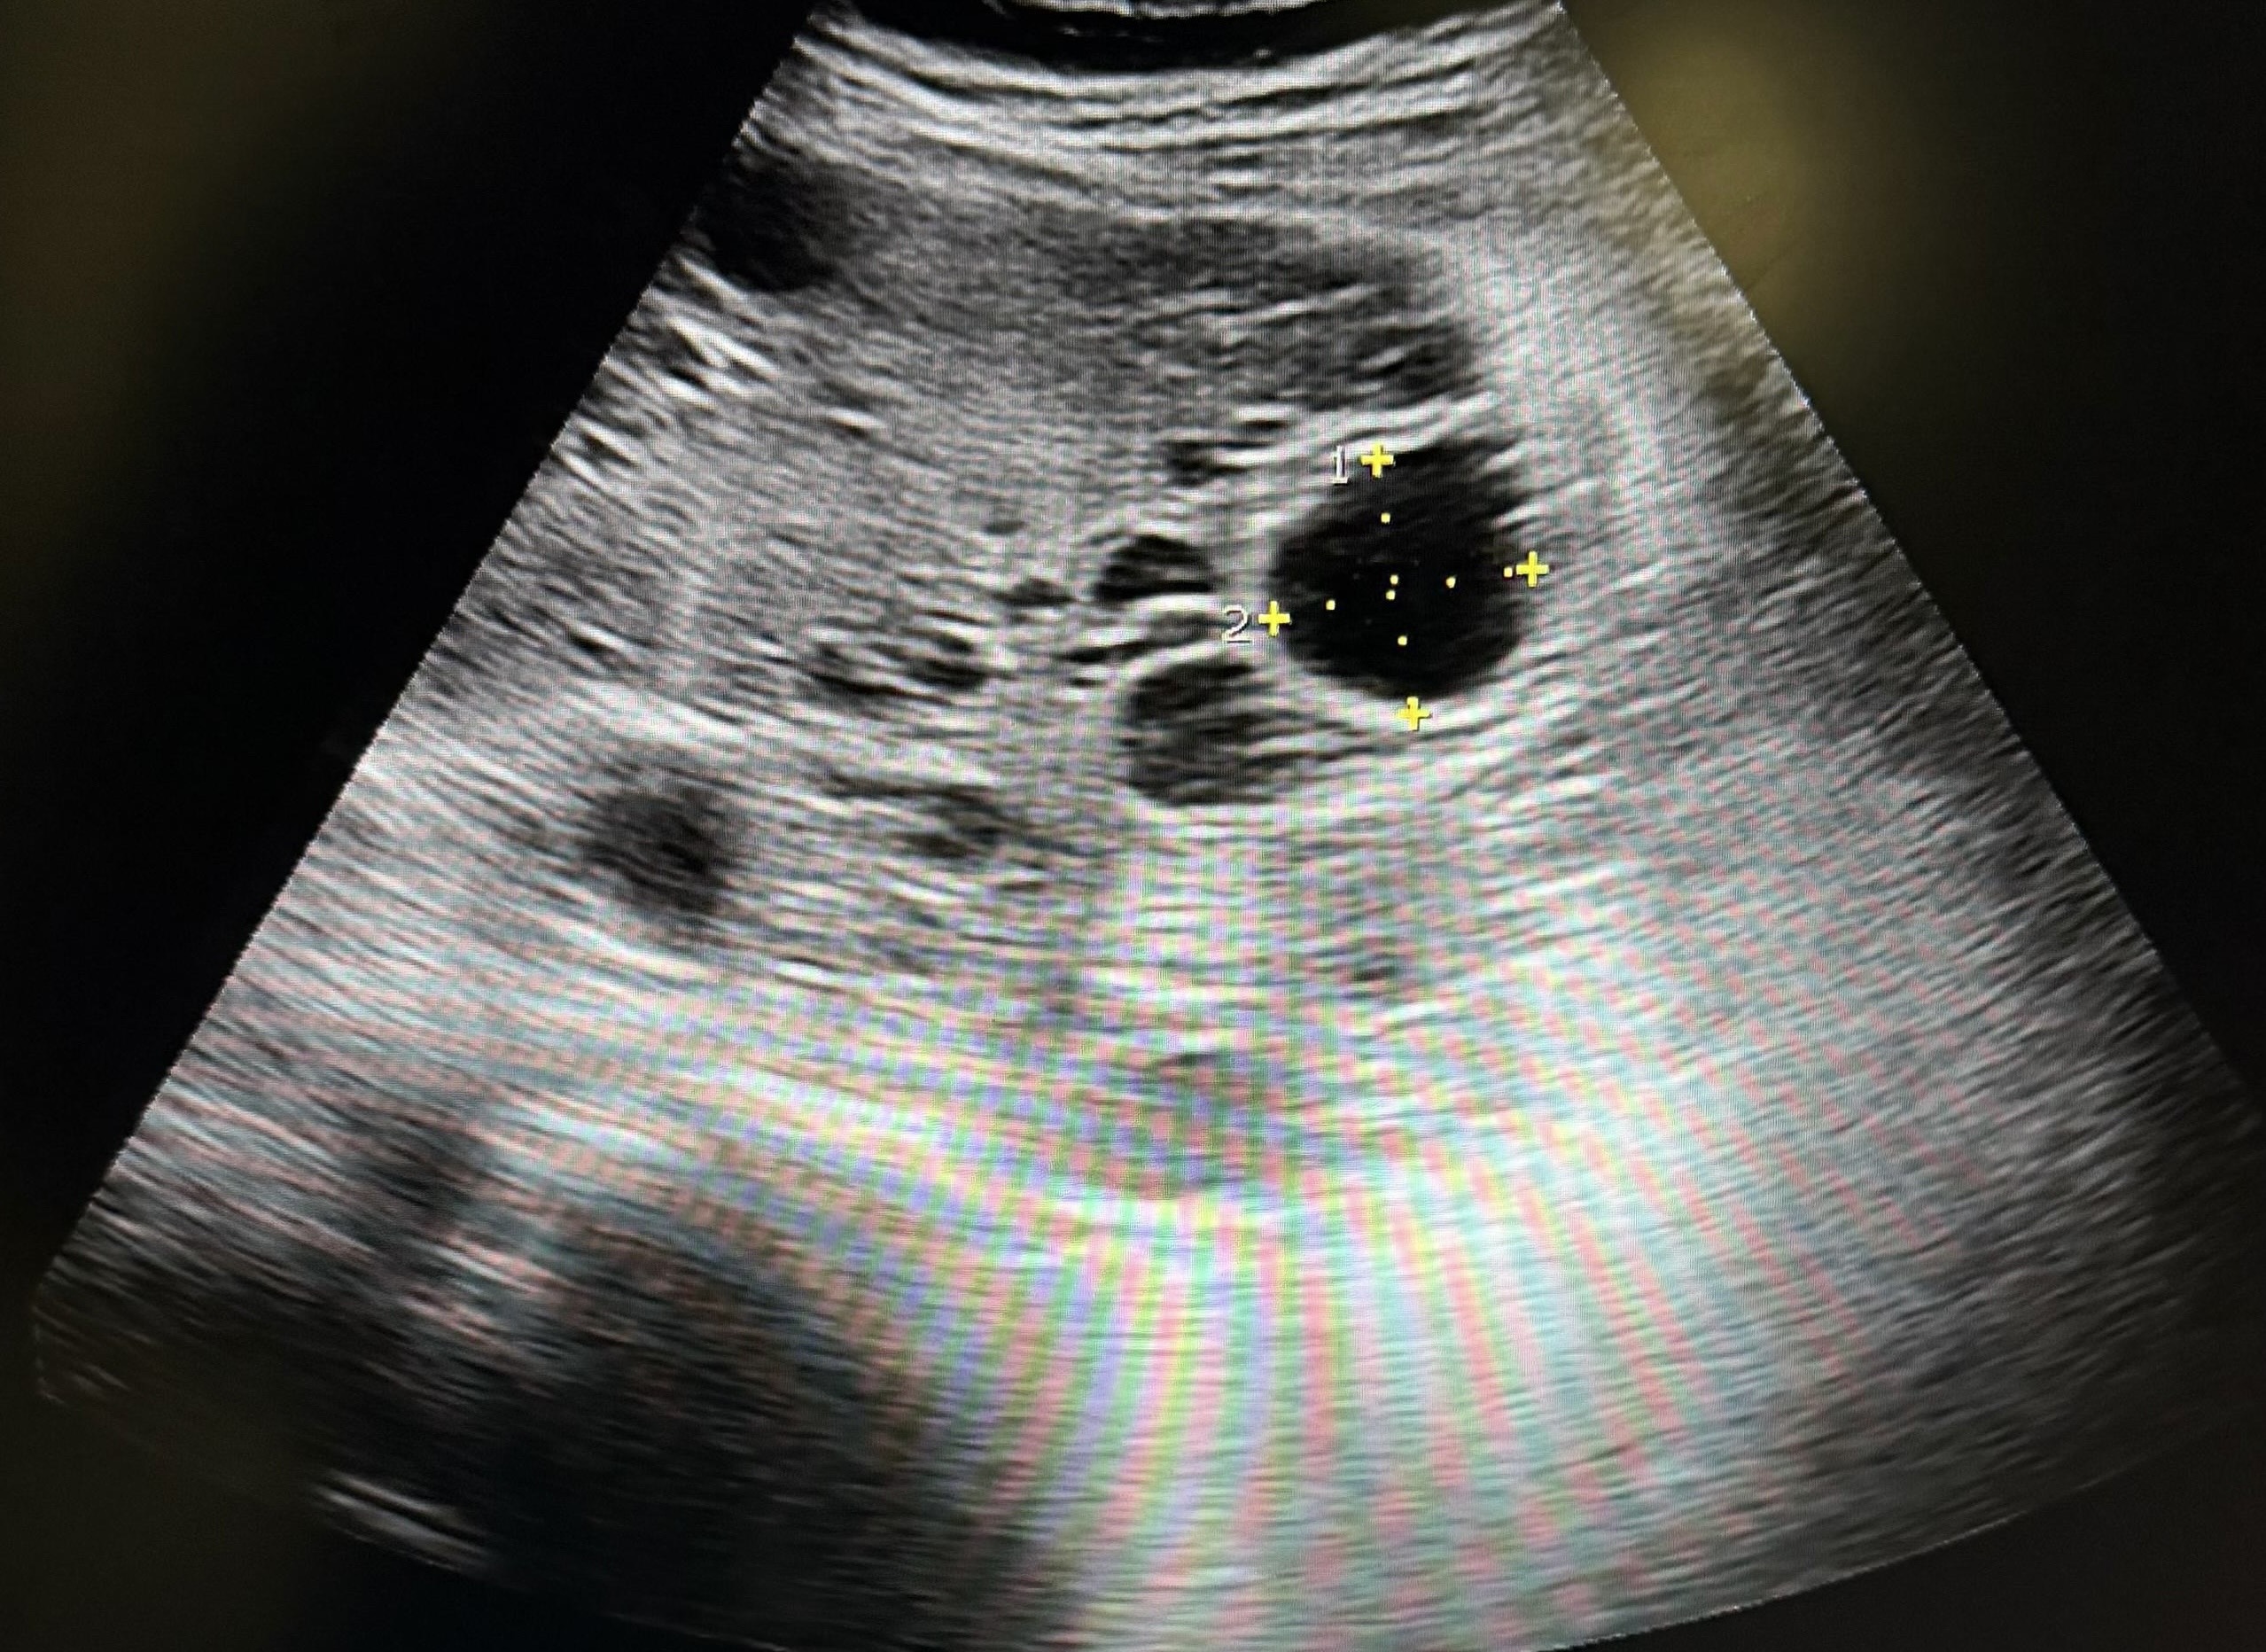

Hallazgos ecográficos

Imágenes quísticas hepáticas múltiples, sugerentes de ser quistes simples hepáticos; debiendo hacer despistaje de enfermedad de Caroli (hamartosis biliar intrahepática).

Ante este hallazgo ecográfico, nos ponemos en contacto con los radiólogos del hospital, les enviamos las imágenes de la eco realizada en consulta y se solicita colangioRMN y analítica sanguínea: